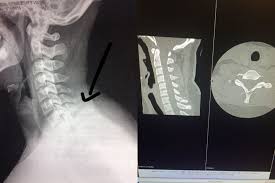

A transverse process fracture at the level of l5 is a surrogate marker of vertical instability of the pelvic fracture due to the attachment of the iliolumbar ligaments. Possible causes, signs and symptoms, standard treatment options and means of care and support. Transverse processes are used as lever arms by the deep spinal muscles to maintain posture and to induce rotation and lateral bending. It may occur as an avulsion fracture due to strong contracture of the muscles. Although the fracture is not associated with spinal cord damage and neurological deficits, the extreme force of the injury can cause visceral injuries and internal hemorrhage. The presence of other injuries might also be assessed due to the level of force needed to break the transverse process. In 78% of transverse process fractures, ct scanning showed that the fracture extended into the transverse foramen. Transverse process fractures caused by stress are likely under detected since even an acute transverse process fracture requires a high index of suspicion to be correctly identified(4,7). Here is an example of a patient with a benign looking transverse process fracture with an associated significant injury to the back. Transverse process fracture you have fractured a transverse process. Thoracic transverse process fractures (ttpfs) are injuries that go unnoticed during traditional autopsies, as demonstrated by a lack of medicolegal publications regarding ttpfs. We retrospectively reviewed the reports of lumbar spine and abdominopelvic ct scans from 2017 and 2018 to classify the types of spine fractures, their mechanism of injury, treatment and. Up to 60% of lumbar transverse process fractures identified on ct will be missed on plain radiographs.

The transverse foramen is an opening on each of the transverse processes of the cervical spine which gives passage to the vertebral artery and vein and a sympathetic nerve plexus. There are two transverse processes that extend off each vertebra in the details: Transverse process fractures are common sequelae of trauma, although they are considered a minor and stable lumbar spine fracture. Transverse processes are typically fractured in direct blows from athletics touch or impact from falls from bikes/motorbikes or by heights. However, postmortem computed tomography (pmct) has made detection of this type of injury easy. There are two transverse processes that extend off each vertebra in the spine, one on each side. A transverse process fracture is a break in 1 or more transverse process. In 78% of transverse process fractures, ct scanning showed that the fracture extended into the transverse foramen. A transverse process fracture is considered as a rare injury. A transverse process fracture is a break in 1 or more transverse process. What is a transverse process fracture? Transverse process fractures caused by stress are likely under detected since even an acute transverse process fracture requires a high index of suspicion to be correctly identified(4,7). If ct confirms isolated injury lateral flexion/extension views are indicated to rule out dynamic instability.

However, postmortem computed tomography (pmct) has made detection of this type of injury easy. There are two transverse processes that extend off each vertebra in the details: What is a transverse process fracture? It may occur as an avulsion fracture due to strong contracture of the muscles. It occurs as a result of sudden and extreme trauma. If ct confirms isolated injury lateral flexion/extension views are indicated to rule out dynamic instability. Vertebral angiography, performed in eight patients with fractures involving the transverse foramen, showed dissection or occlusion of the vertebral artery in seven (88%) instances. This part extends out from the side of the main body of the bone (called the vertebral body). A transverse process fracture at the level of l5 is a surrogate marker of vertical instability of the pelvic fracture due to the attachment of the iliolumbar ligaments. We retrospectively reviewed the reports of lumbar spine and abdominopelvic ct scans from 2017 and 2018 to classify the types of spine fractures, their mechanism of injury, treatment and. Up to 60% of lumbar transverse process fractures identified on ct will be missed on plain radiographs. In 78% of transverse process fractures, ct scanning showed that the fracture extended into the transverse foramen. Transverse process fractures identified on helical computed tomography (ct) scans without the presence of any other fracture or.